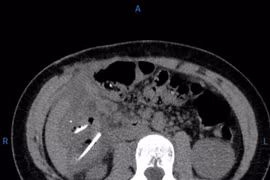

Hơn 1 tháng đau bụng nôn ói cấp cứu phát hiện 10 cục nam châm dính 2 đoạn ruột non gây thủng và tắc ruột. Nuốt dị vật tiêu hóa là một tai nạn sinh hoạt khá thường gặp trong cuộc sống hằng ngày nên cha mẹ cần chú ý.